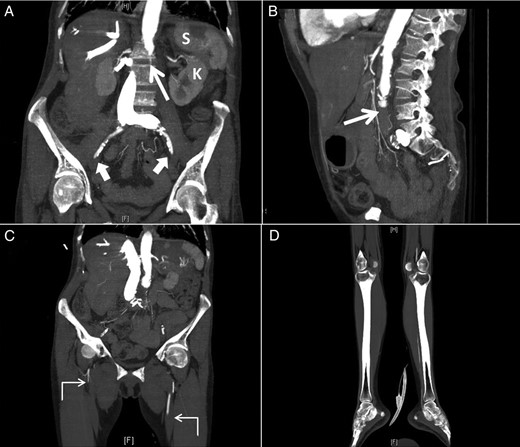

Repeated CT scan of the head 24 h later confirmed the diagnosis of an evolving large right hemisphere infarction involving both anterior and middle cerebral arteries territory with midline shift (Fig. 3A and B). Hemicranial decompression was performed and a follow-up CT scan of the head, 24 h later, showed transcranial herniation of the right cerebral hemisphere with reduction of the midline shift (Fig. 3C and D). Likewise, because of the multiplicity of the emboli, she also developed occlusion of the aorta as well as in both femoral systems and right popliteal artery that required corresponding embolectomies and bilateral aortofemoral bypass surgery. The pathological examination of the emboli confirmed the diagnosis of atrial myxoma.

Axial (A and C) and coronal (B and D) CT images of the brain showing a large infarct in the area of the right middle cerebral artery before (A and B) and after (C and D) right hemicranial decompression with transcranial herniation of the right cerebral hemisphere (interrupted curved arrows).